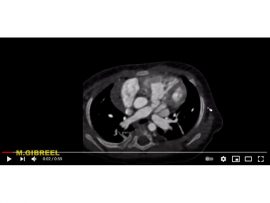

Tricuspid atresia , pulmonary atresia intact IVS Ductus dependent pulmonary circulation LMCA aneurysm Mohamed Gibreel , FEBR (Fellowship of Egyptian Board of Radiology ) Cardiac..